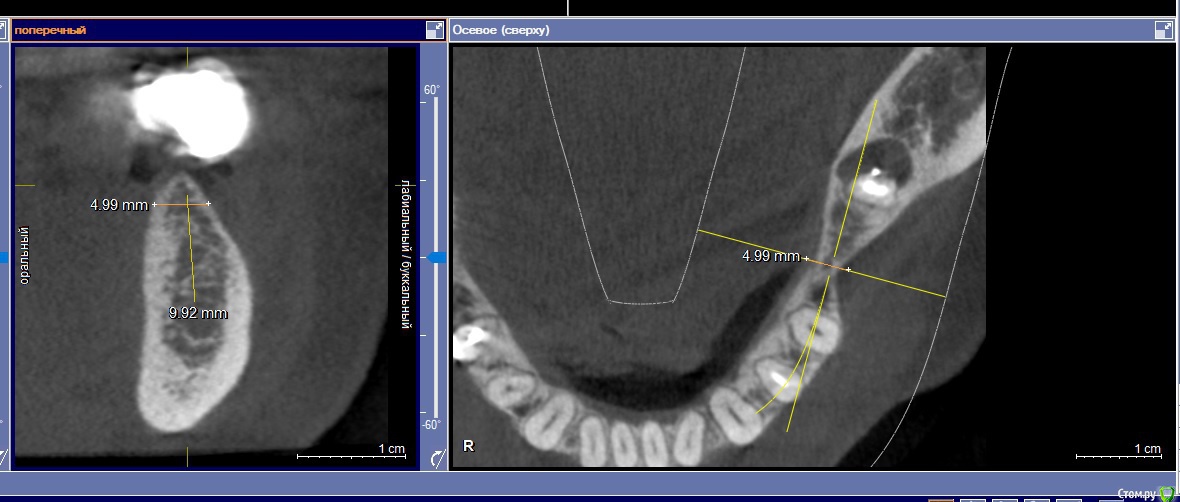

igorgergg Опубликовано 19 июня, 2018 Автор Поделиться Опубликовано 19 июня, 2018 А есть ли такая острая необходимость в нкр? Покажите снимкиПо ширине 5 мм Ссылка на комментарий

колесников Опубликовано 19 июня, 2018 Поделиться Опубликовано 19 июня, 2018 И? Вполне себе размер. Покажите скрины кт 1 Ссылка на комментарий